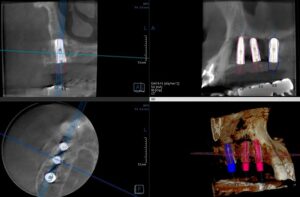

お蔭さまで、無事に今年も診療がはじまり、 最初のインプラント埋入手術をしました。 骨の幅も高さも十分あり骨量・骨質共に問題の無い症例でした。手術も2時間程度で終わりました。 下のレントゲン写真はCTの写真です。左下が水平の断面で上の二つが前 […] 本文を読む